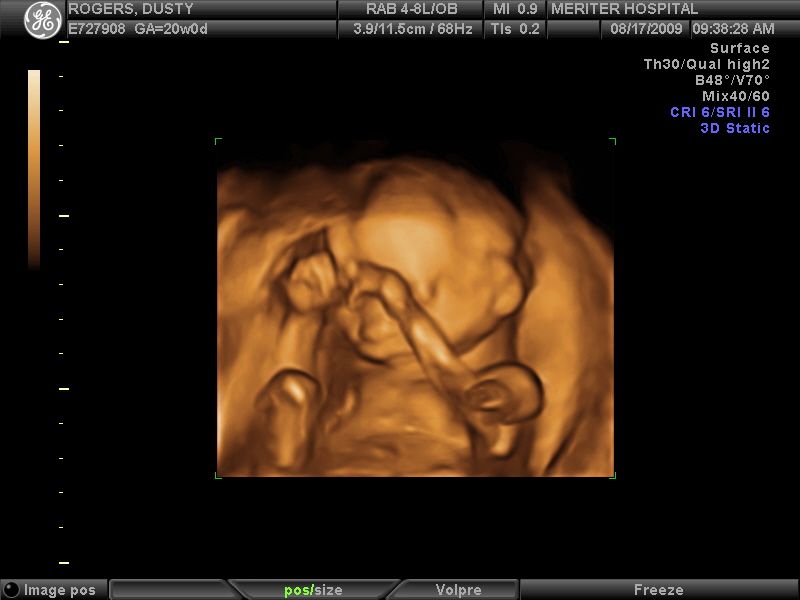

I am so in love with this picture–I can’t stop staring at it. She has her hands up in front of her face like she’s being all bashful and thinking, “No pictures, please.” And look at that cute little nose! Oh how I love our little girl!